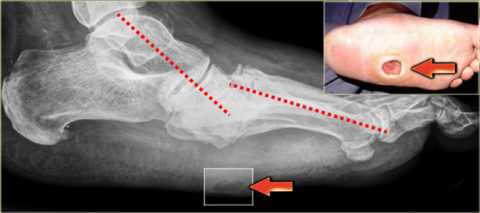

| Признаки диабетической стопы проявляются при снижении чувствительности стопы, повышении болевого порога, изменении формы, деформации, утолщении кожи и появлении мозолей (чаще на головках II-III метатарзальных костей) и сопровождаются гиперкератозом и сухостью кожи, незначительными болями или без них. Стопа Шарко или периферическая нейропатия провоцирует развитие остеоартропатии – синдромокомплекса с асептической костной деструкцией суставов и костей, что можно увидеть на рентгенограмме. При этом страдают голеностоп, плюсна и предплюсна:

Длительный деструктивный остеопороз, остеолиз, гиперостоз приводит к синдрому диабетической стопы: деформации костей, суставу Шарко. Тогда стопа будет напоминать мешок с косточками. Понадобятся срочное лечение и ортопедическая обувь.